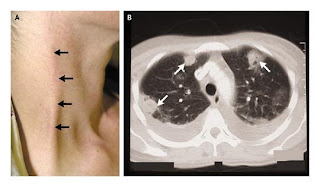

A patient with Lemierre's syndrome: A. Thropbophlebitis of external jugular vein.  Bilateral pleural effusion and multiple areas of consolidation with cavitation

Most patients with Lemierre’s syndrome are older than 10 years.7 The patients look toxic and manifest fever, sore throat, cough neck, pain, dyspnea, and arthralgia. Palpable jugular arch can be detected in about 20% of patients. Swelling and tenderness at the angle of the jaw and along the sternocleidomastoid muscle with signs of severe sepsis along with evidence of pleuropulmonary emboli, is very suggestive of thrombophlebitis of the internal jugular vein.6